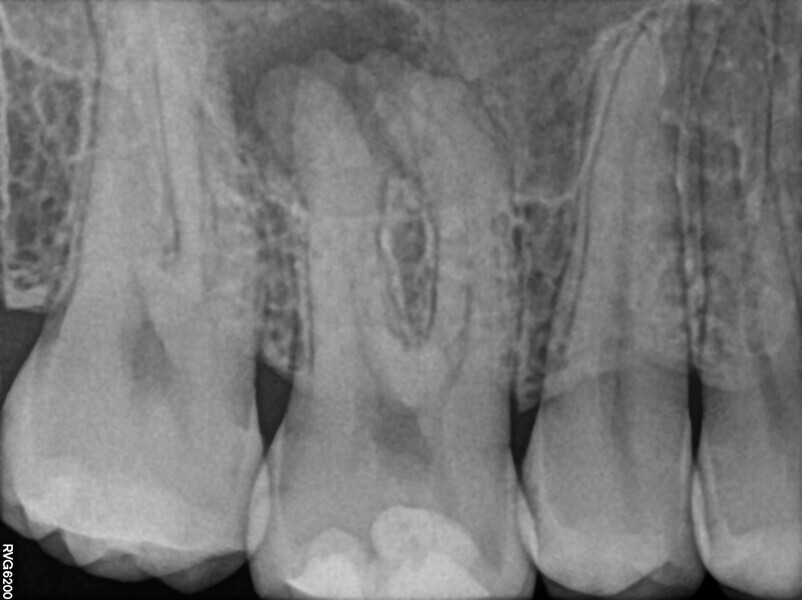

A 25-year-old female patient presented to the office owing to constant pain related to the mandibular left first molar. Pulp necrosis was diagnosed. After the emergency appointment, the patient was referred for complete treatment. The tooth was treated in the same manner as described in the previous paragraphs. After creation of the access cavity, the orifices were located. In the root chamber, the orifices of the MB, mesiolingual, DB, distomesial and distolingual canals were present. After pre-flaring and preparation of the middle third, the LPE enhanced irrigation protocol with the SkyPulse laser was performed. After the irrigation protocol in the mesial root, the irrigants started to flow between lingual and buccal canals. Such an observation suggested to the operator that some space in the isthmus had been created. It is worth mentioning that at this stage apical enlargement was not performed. Final preparation of all five canals was performed with the reciprocating file, and the final irrigation protocol was performed as in the previous case. The radiograph clearly revealed that the isthmus space was filled with the sealer. The radiograph and CBCT image revealed that there were four portals of exit in the mesial root.